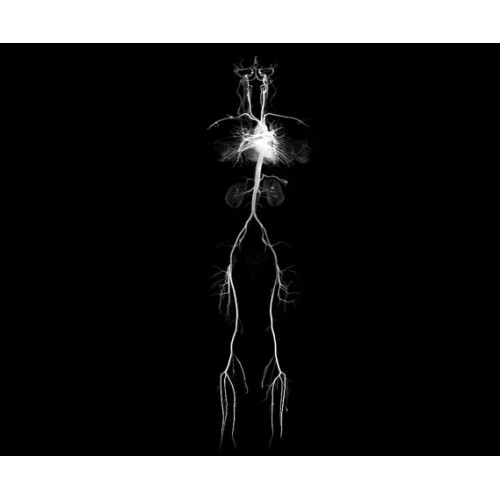

МР-ангиография

Да

• CVWorks — приложения для кардио-визуализации помогут получить данные о морфологии, динамике кровотока, функции миокарда, а также информацию о структуре сосудов и динамике кровотока.

• NeuroWorks — универсальное решение для визуализации анатомии головного мозга, позвоночника, сосудов и периферических нервов с четкой дифференциацией тканей.